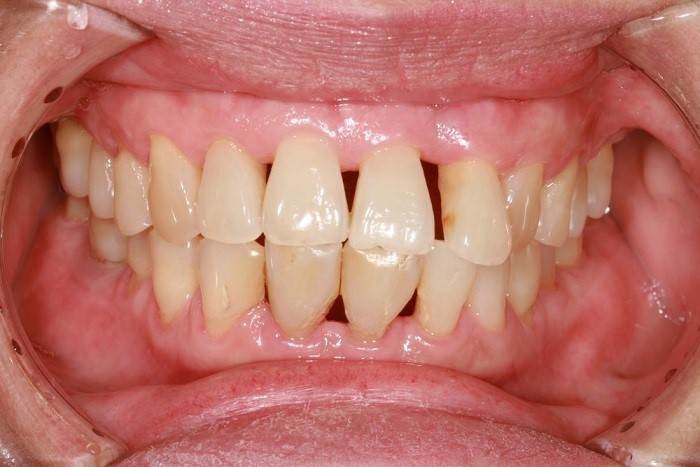

در بیماریهای پیشرفته لثه، مانند پریودنتیت، پاکت لثه به عنوان یک فضای ناشی از التهاب و عفونت در لثه شکل میگیرد. این التهاب و عفونت باعث چسبندگی بافت لثه به دندانها میشود و در صورت گسترش، عمق پاکت به بیش از 5 میلیمتر میرسد. در این موارد، جراحی فلپ به عنوان یک روش درمانی مؤثر برای کاهش عمق پاکت لثه و بهبود وضعیت لثه استفاده میشود.

پریودنتیت به عنوان یک بیماری شدید و پیشرفته از بیماریهای لثه شناخته میشود و باعث تخریب استخوان و بافت لثه میشود. این التهاب و عفونت باعث جدا شدن لثه از دندانها شده و باعث افزایش فضای پاکت لثه میشود و منجر به نفوذ باکتریها به بافت لثه و استخوان خواهد شد و در نتیجه ممکن است منجر به آسیب جدی به استخوان شود.